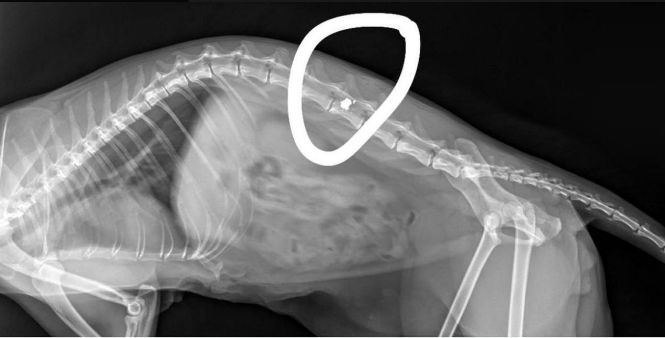

На улице 230-й Стрелковой Дивизии мужчина стрелял из пневматического оружия по животным. Одна из пуль попала в хребет котенка.

Пуля попала в хребет моего маленького котика, сейчас он находится в ветбольнице в тяжелом состоянии, неизвестно, выздоровеет ли, – написали они.